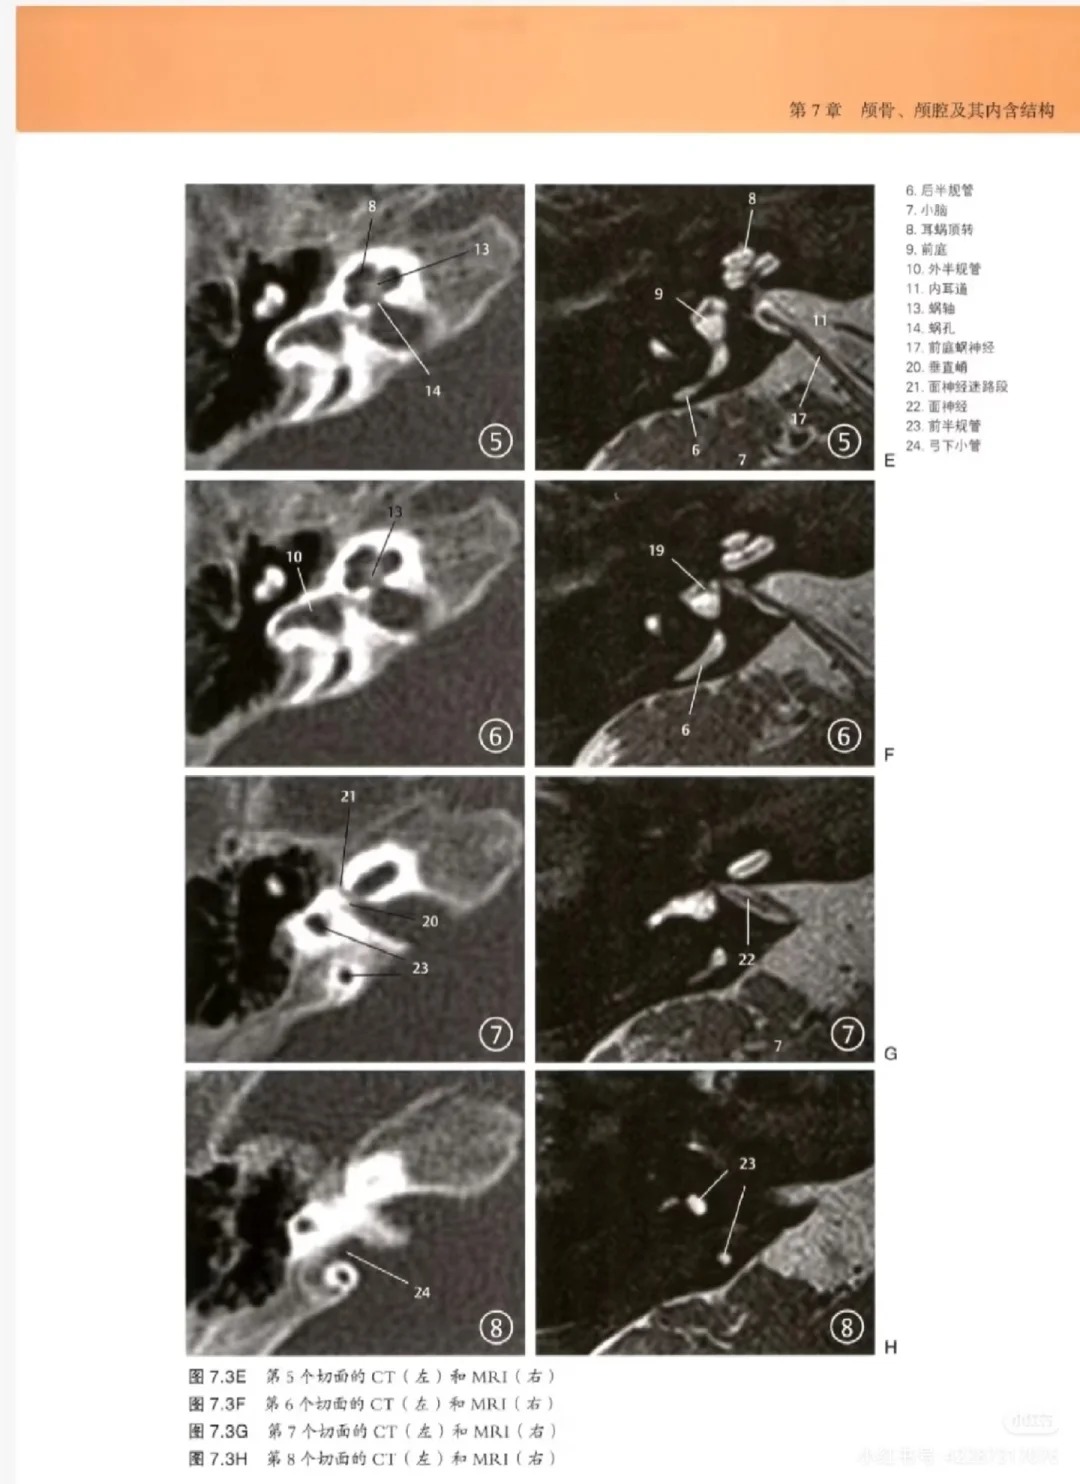

2. 影像与解剖深度结合,破解看片难题:这是本书的核心王炸卖点,每一张颅脑影像图旁边,均配套高清解剖图+手绘示意图,精准对应解剖结构与影像表现,清晰标注关键部位,让使用者能快速将影像表现与解剖结构关联起来,彻底解决“对着片子找不着北、看不懂脑回路”的核心痛点,提升看片与诊断能力。

4. 高清大图,标注精准,直观易懂:全书采用高清大图呈现,影像图、解剖图清晰可辨,标注精准细致,关键解剖结构、病变部位一目了然,对于影像这种“看图说话”的学科,能大幅提升看片与学习效率,无论是临床看片还是日常学习,都能快速抓取核心信息。

• 影像+解剖对照篇:每一张影像图配套高清解剖图+手绘示意图,精准对应解剖结构,标注关键部位,帮助使用者快速关联影像与解剖,看懂颅脑结构。